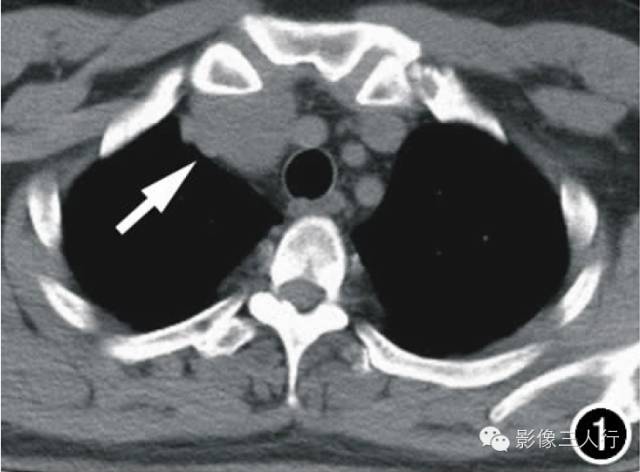

图1横轴面CT平扫示前上纵隔偏右侧一团块影(箭),大小约3.5cmX3.2cm,边界尚清,密度均匀,CT值约44HU,局部血管受压推移。图2横轴面CT增强扫描动脉期示肿块显著均匀强化(箭),CT值为95HU。图3横轴面CT增强扫描延迟期示肿块持续强化(箭),CT值为158HU。图4镜下示细胞排列呈编织状、旋涡状,疏密不均,细胞呈梭形、短圆形,胞核红染,部分细胞出现不典型增生(X400,HE)。